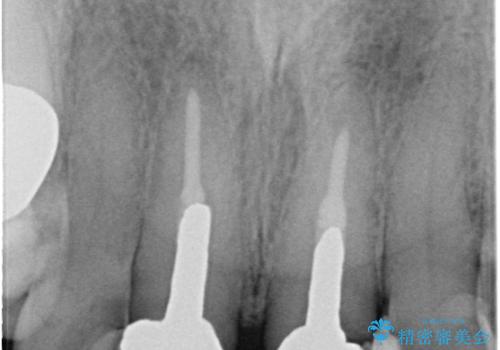

- 奥歯がなくて咬めないのと、全体的に見た目をよくしたいとのことで来院されました。

下顎の両側の奥歯が欠損しており、入れ歯をお持ちでしたが、うまく咬めずにほとんど使用していない状態でした。

上顎は全体的にクラウンの入れ替えと、下顎はインプラントの提案もしましたが、希望されなかったのでノンクラスプデンチャーの製作をする治療計画としました。

奥歯が欠損しており、上下の前歯が強く咬合する可能性があったので、上顎前歯の裏側は金属のものにしました。